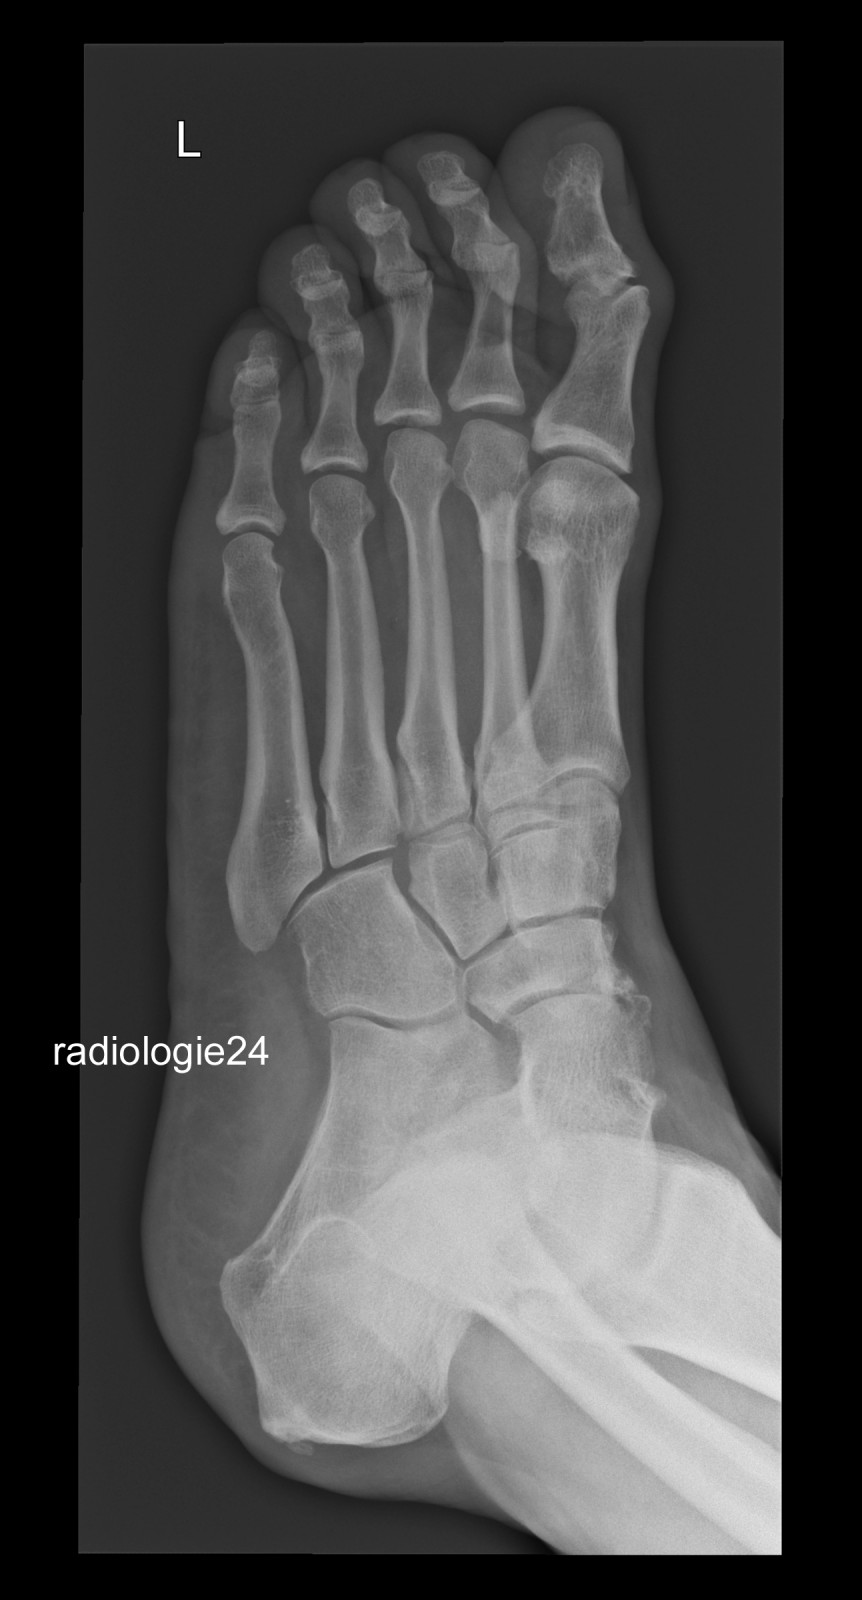

Röntgenfall des Monats September 2018 mit Auflösung

52 jähriger Patient Fehltritt beim Wandern. Schmerzen Mittelfuss. Ihre Diagnose? Weitere radiologische Diagnostik notwendig?

Bild vergrössern

Link zur Auflösung mit ausführlichem Befund:

https://www.radiologie24.ch/radiologie-mediathek/roentgenfall_des_monats